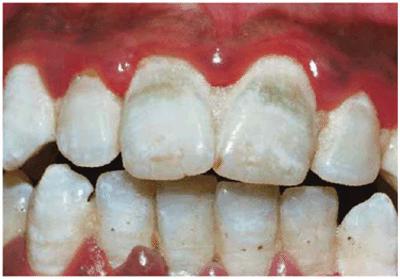

Figure 16-3: Green stain associated with poor oral hygiene and gingival inflammation.